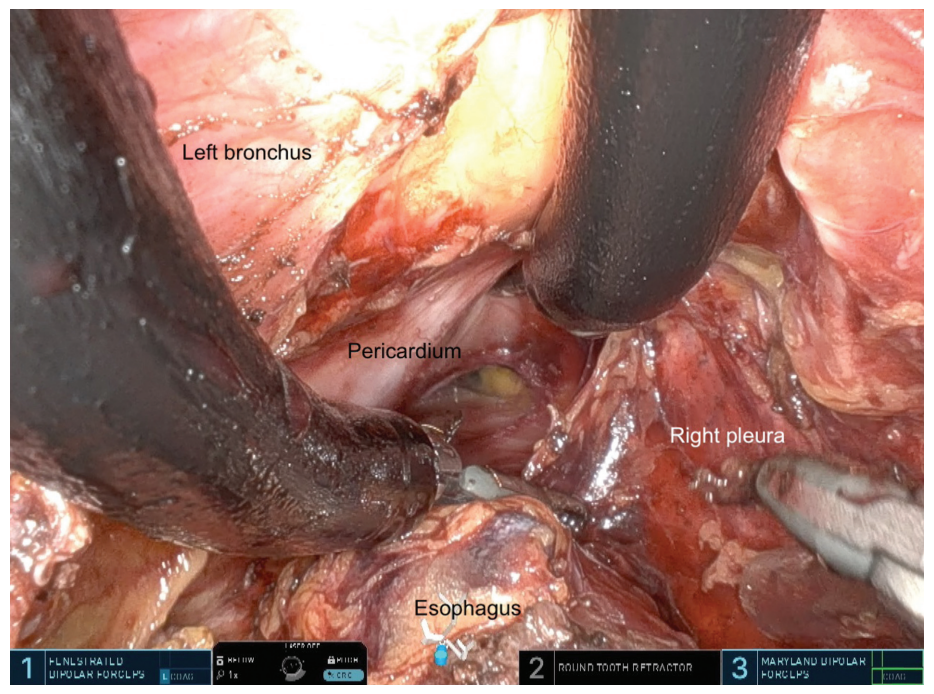

经颈SP阶段:在左锁骨上方约两根手指处,胸锁乳突肌前内侧皮肤做一3cm交叉切口(图1A)。颈阔肌和直颈肌被横断。左胸锁乳突肌向外侧旷置,尾部甲状腺血管横断,甲状腺下极向内侧旷置。可见左侧喉返神经,并通过神经监测其功能。然后,将左颈总动脉从周围组织内侧游离开,直到看到食管左侧。食管准备后,将悬吊线置于食管周围,以用于其在上纵隔准备期间牵拉。插入大切口 (2.7–7 cm) SP接入端口套件,并施加8mm Hg 的压力以诱导二氧化碳纵膈气肿 (图1B)。为了有效管理有限的术野空间,采用高流量气腹机,确保在有限的工作空间内保持稳定的术野。达芬奇SP患者侧推车位于患者右颅侧,机器人已对接。器械的选择由外科医生自行决定。我们在位置1上使用有孔双极镊子,在位置2上使用圆齿牵开器,在位置3上使用马里兰双极镊子。30度相机放置在向上的“眼镜蛇”位置。暴露气管左侧并向右缩回以识别左侧喉返神经,并采用神经监测进行指导。随后沿左喉返神经解剖上纵隔食管和周围淋巴结清扫。使用马里兰双极钳,将食管从气管膜部分离,以脊椎作为纵隔解剖的背侧和横向标志。沿着这些平面描绘壁层胸膜并作为进一步解剖的边界。随后,主动脉弓与左喉返神经一起被识别,并通过神经监测进行确认。随后以奇静脉和降主动脉作为关键标志,对食管和食管旁淋巴结进行环形解剖(图2A)。此时,在腹部阶段应用吲哚菁绿 (ICG) 染料来可视化并保留胸导管(图2B)。通过同时向后和向上牵拉食管,可以将气管向下追踪到隆突,在此处识别并解剖左、右主支气管和隆突,使其于食管分离。注意不要损坏这些结构。经颈途径尤其有利于隆突淋巴结清扫。在隆突下水平和远端,当食管向裂孔自由游离时,位于前侧的心包和左右壁层胸膜充当标志(图3)。

图3. 在隆突下水平和远端,心包(腹侧)和左右壁层胸膜是朝着裂孔方向安全游离食管的标志。